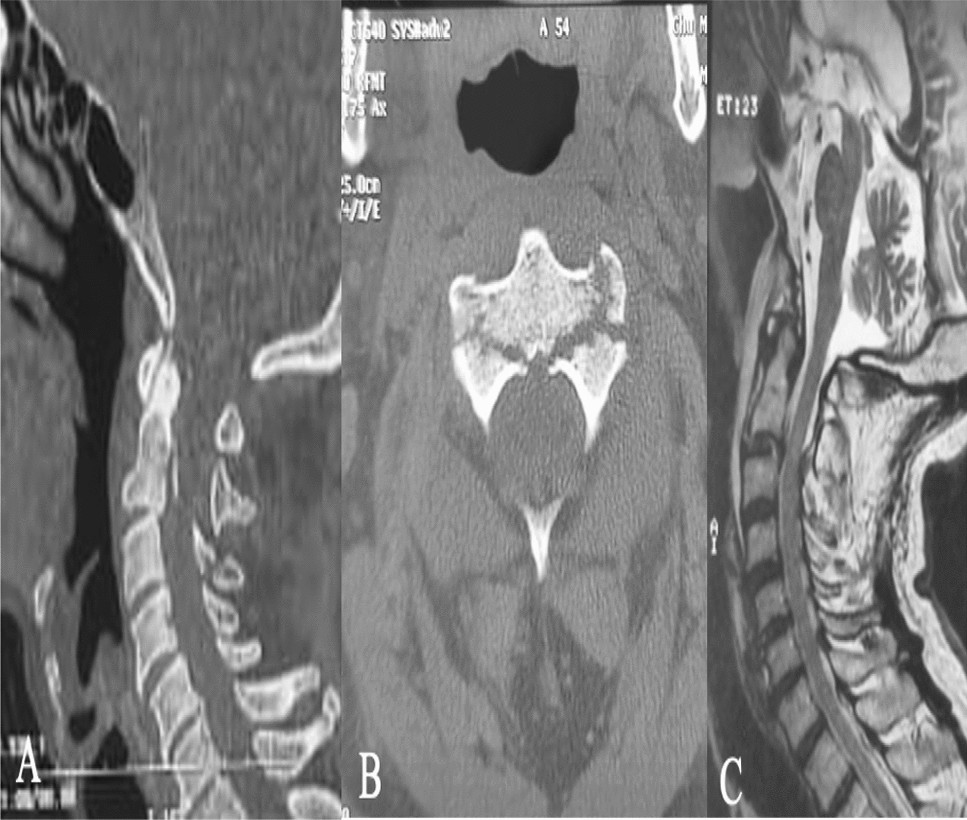

Hangman's fracture: a clinical review based on surgical treatment of 15  cases | Neurosurgical Review, image size:2051x1587

Hangman's fracture: a clinical review based on surgical treatment of 15 cases | Neurosurgical Review